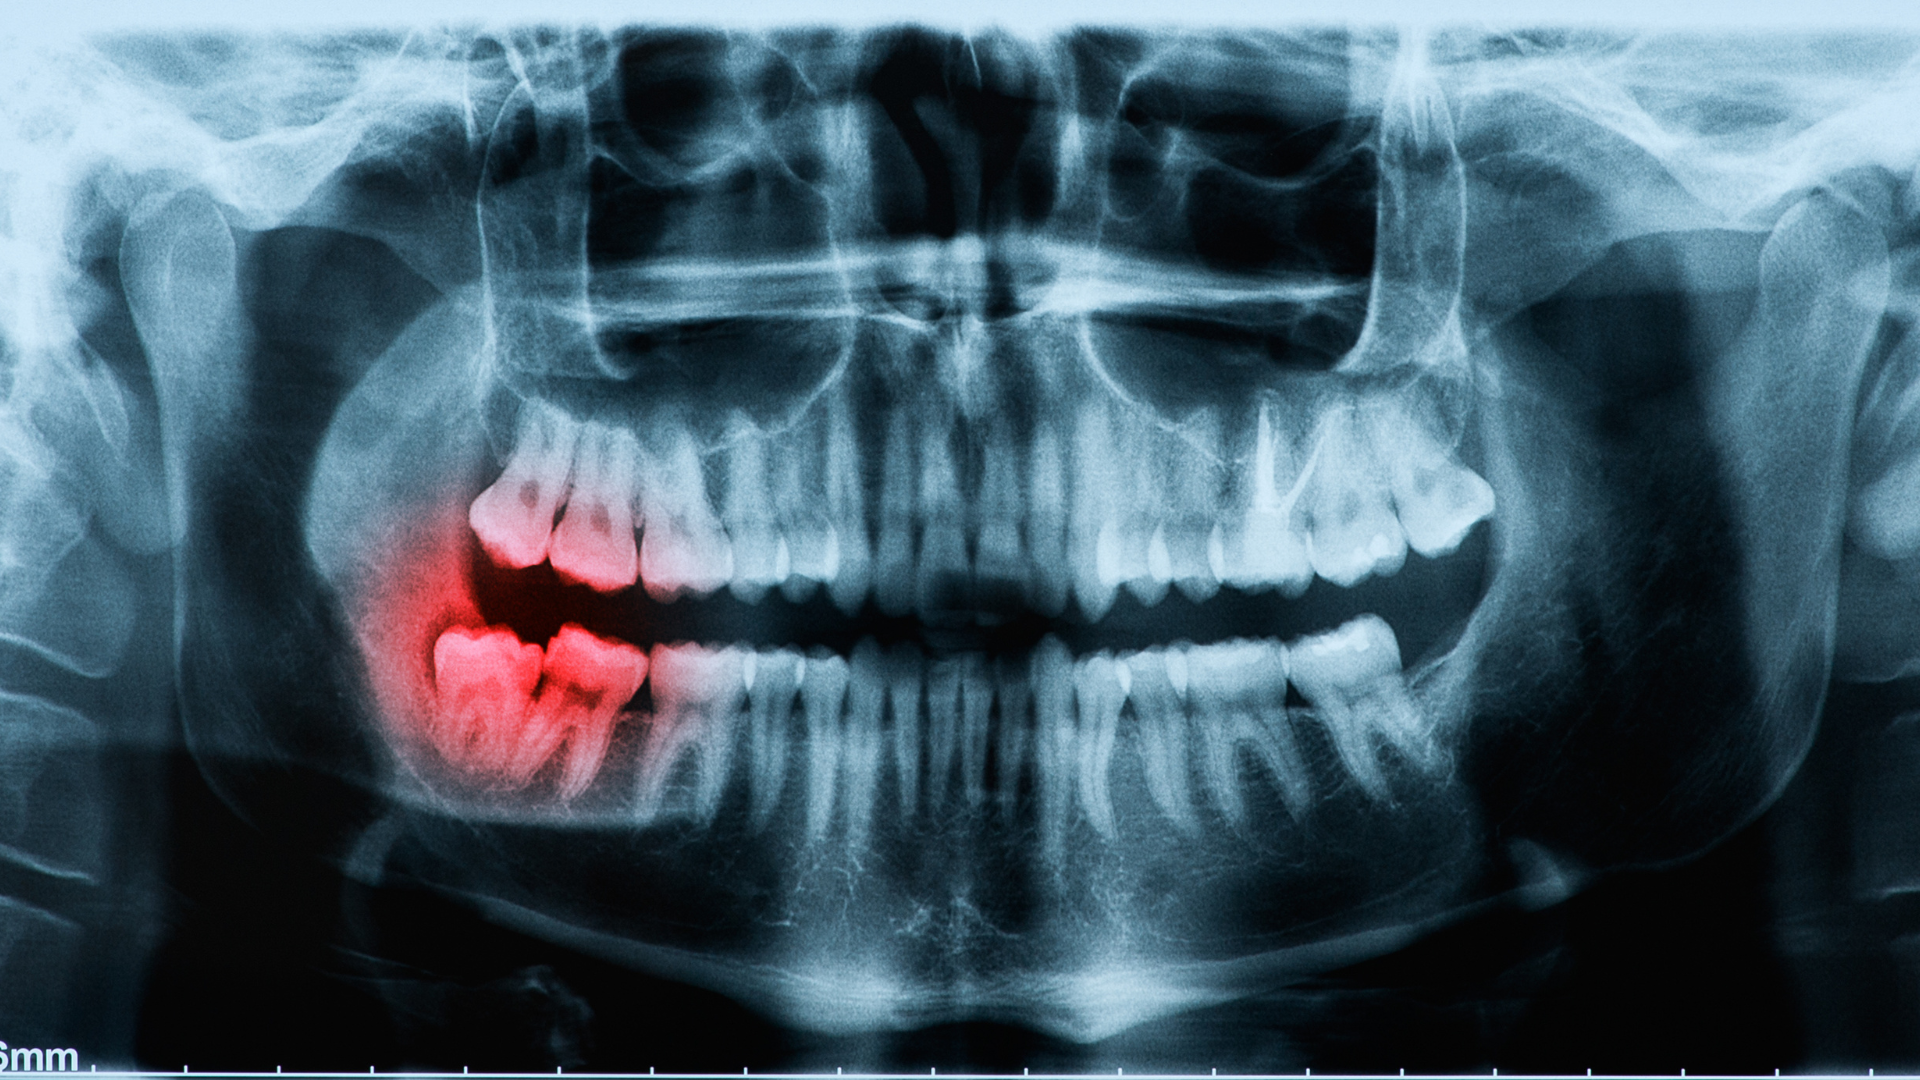

- Có thể nhìn thấy phim X-quang hoặc hình ảnh chụp răng cho thấy răng khôn nghiêng về phía răng kế cận hoặc ra má.

- Chụp phim X-quang (OPG) hoặc CBCT: Để xác định phương hướng mọc, độ sâu, sự tiếp xúc với răng số 7 hoặc dây thần kinh hàm dưới.

- Đánh giá nguy cơ và chỉ định: Dựa vào triệu chứng, mức độ lệch, không gian hàm và khả năng vệ sinh.